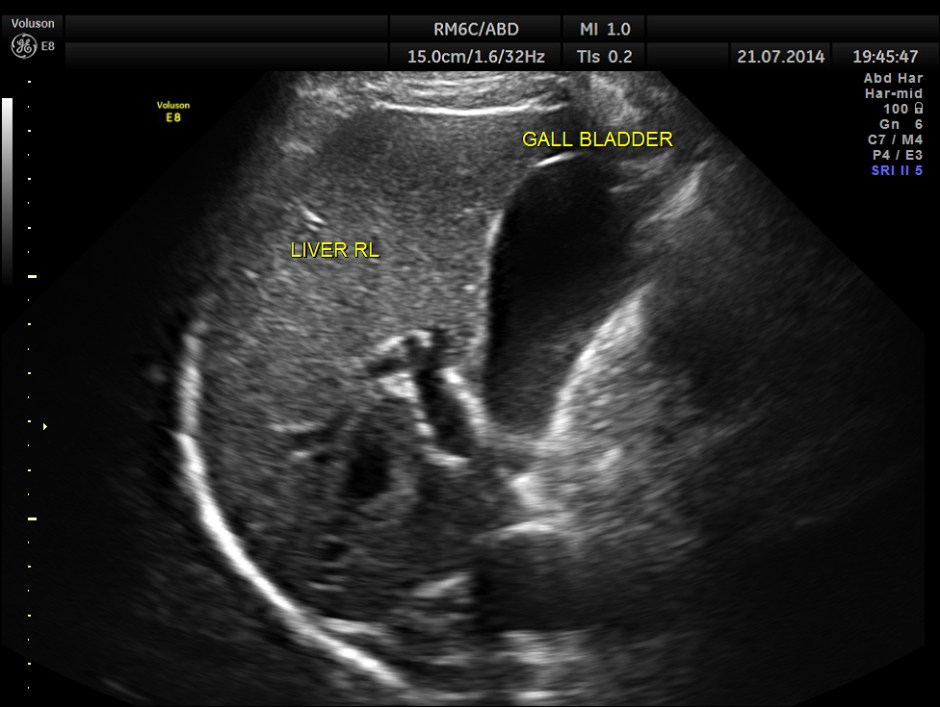

This was a 42-year-old gentleman , a known case of Insulin dependant Diabetes Mellitus. He was being evaluated by his physician for loss of weight and abdominal pain of a few months duration.

His abdominal ultrasound pictures are given below.